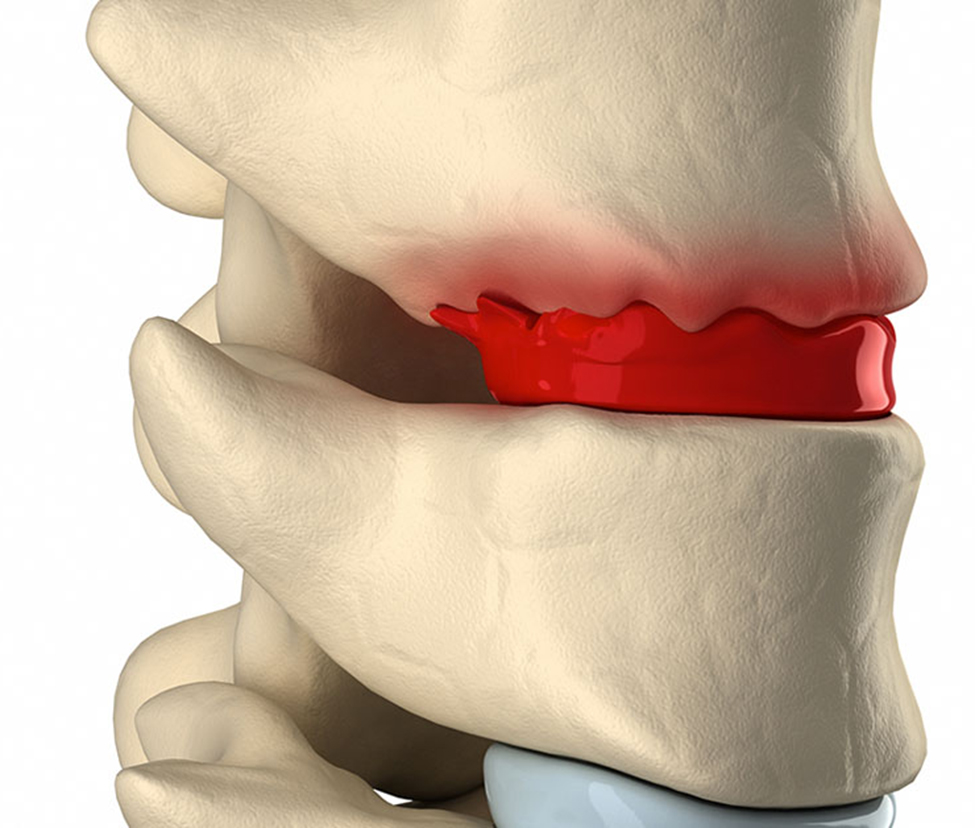

Phục hồi chức năng bệnh lý cơ xương khớp